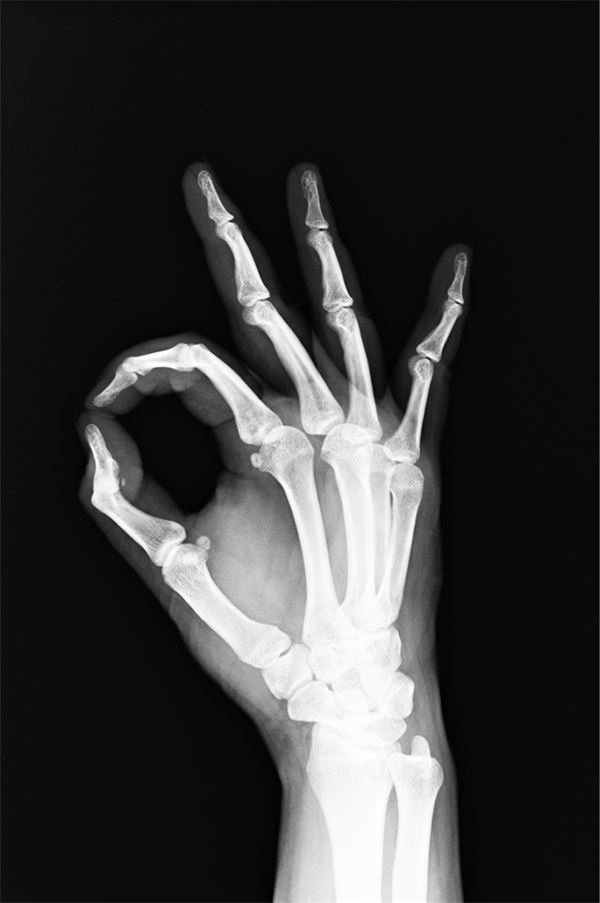

В 1895 году немецкий физик Вильгельм Конрад Рентген (1845–1923) совершил очередной переворот в науке. Он ставил опыты с так называемой катодной трубкой (баллон с двумя электродами) и обнаружил лучи, которые обладали способностью пронизывать практически все предметы, которые взволнованный исследователь помещал в поле их действия: доски, листы картона, алюминиевые пластины… Но самым удивительным было то, что, вытянув руку между источником лучей и световым экраном, Рентген смог во всех подробностях рассмотреть скелет кисти.

Открытые лучи исследователь назвал «Х-лучами», желая таким образом подчеркнуть их необычность и загадочность. Опубликовав несколько работ, которые, впрочем, не раскрыли окончательно природу загадочного «Икса», Рентген занялся другими исследованиями. А суть открытия пояснили в 1912 году физики Вальтер Фридрих (1883–1968) и Пауль Книппинг (1883–1935). Их вывод был таков: рентгеновские лучи – не что иное, как электромагнитные колебания, во многом схожие с обычным светом, но обладающие значительно большей частотой и меньшей длиной волны. Этим и объясняются их удивительные свойства.

«Х-лучи» имели (и имеют до сих пор!) огромное значение для медицины, физики, техники. Диагностика заболеваний, борьба с контрабандой, экспертиза произведений искусства – во всех этих областях с рентгеновскими лучами связано немало интересных историй. В начале ХХ века изобретение Рентгена активно использовалось для проверки военной техники и качества материалов.

В 1901 году Вильгельм Рентген стал первым в истории Нобелевским лауреатом в области физики

Иллюстрация к книге — 99 секретов физики [i_030.jpg]

Рентгенография применяется для диагностики